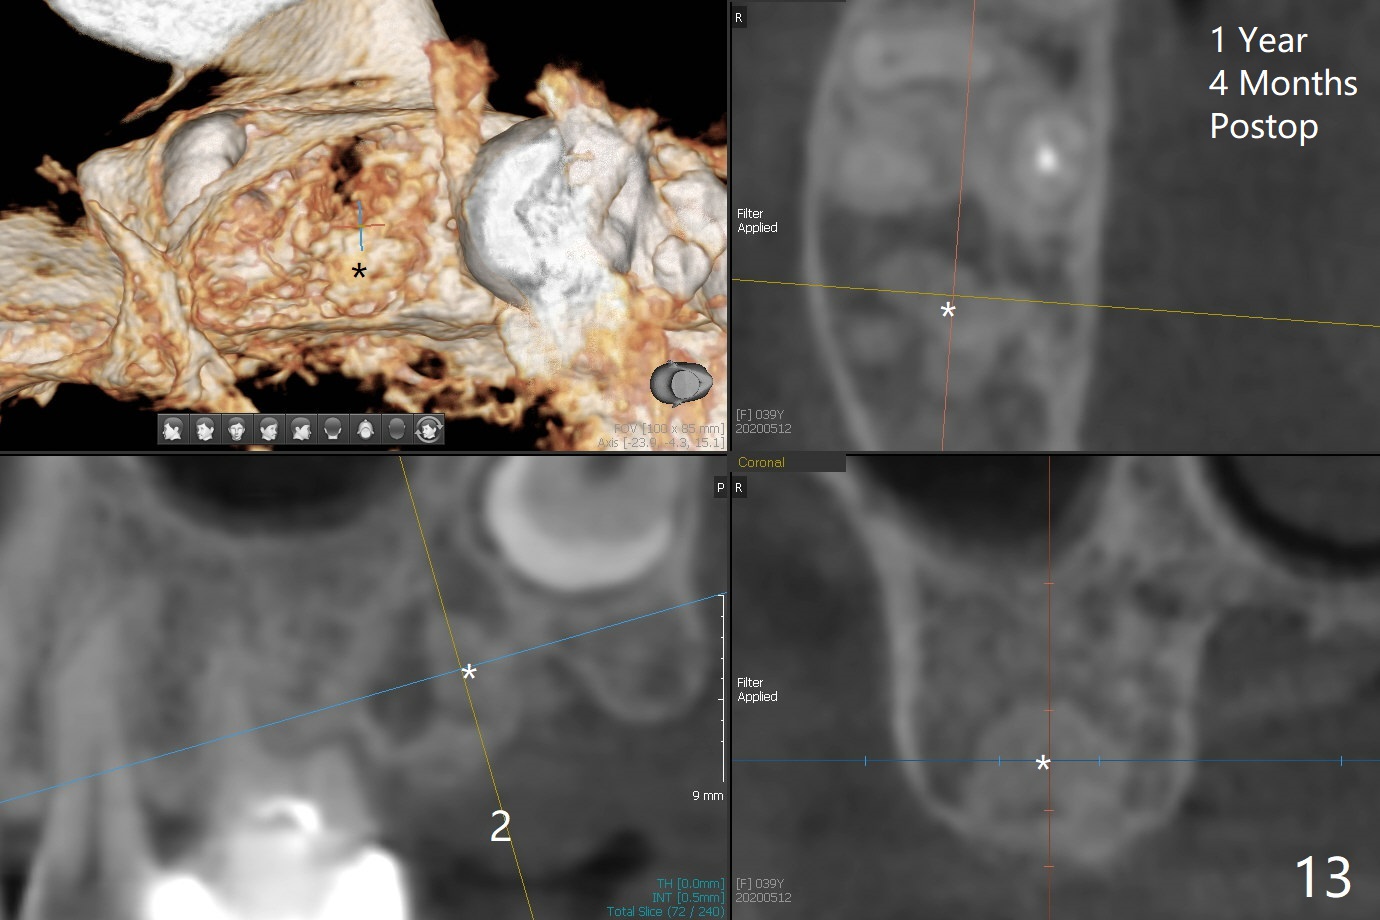

The socket of #2 heals 13 days postop; it appears that the bone graft remains in place (Fig.7,8 *). The patient is instructed to return in 3-4 months for impression and CT for guide. The socket heals 4 months postop (Fig.9,10). She plans to have implant next year, since she wants to add another insurance. The patient returns for implant without removal of the third molar 2 years 4 months post socket preservation (Fig.11). A 5x7.3 mm implant can be placed without invading the sac of the impacted third molar (Fig.12). In fact the lab has a better plan. A lump of bone forms in the previous socket 1 year 4 months postop (Fig.13 *). The ridge is wide and dense (Fig.14). A narrow implant placed oblique could be longer (Fig.15), as compared to a wide, short one (Fig.12).